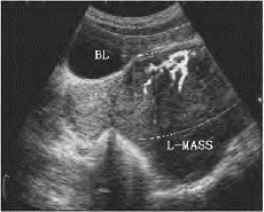

图33-17B 输卵管癌声像图

图为左侧附体区输卵管积水(L-T-F),其中有团状实性包块(↓←)与管壁界限不清